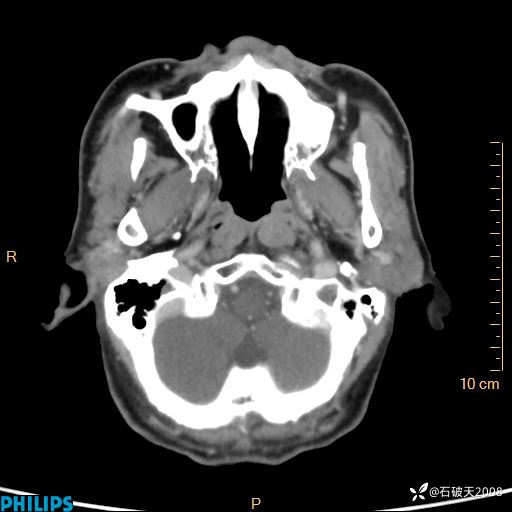

静脉期